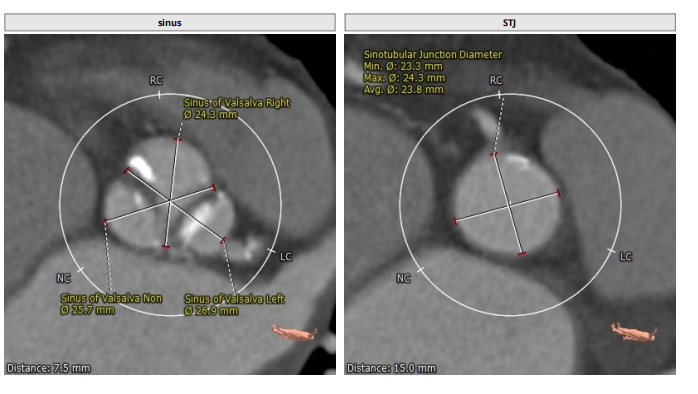

术前CT分析

三叶瓣,轻中度钙化,右无疑似融合,左冠开口高度低,右冠开口高度不高,法式窦结构不大,左室大小可,升主动脉未见明显扩张。小窦,小瓣环,准备瓣膜型号L23。